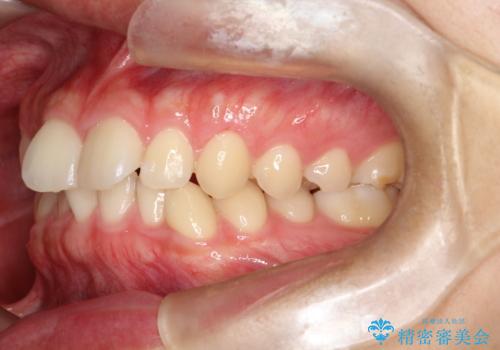

マウスピース矯正で前歯のガタツキを改善! 短期間で治療完了

- 前歯のガタツキが気になるとのことで来院されました。

マウスピース矯正で治療することとしました。